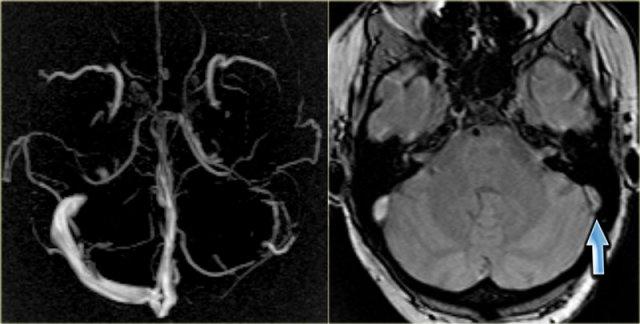

Xoang ngang kém phát triển (hypoplastic)

Kém phát triển (hypoplasia) và bất sản (aplasia) xoang ngang phải hoặc trái là một phát hiện thường gặp.

Tình trạng này có thể dễ dàng bị nhầm lẫn với huyết khối xoang, do trên MRA một trong hai xoang ngang không được hiển thị.

Khi nghi ngờ có xoang ngang kém phát triển, cần quan sát kích thước của lỗ tĩnh mạch cảnh (jugular foramen).

Các hình ảnh bên trái là của một bệnh nhân có xoang ngang trái kém phát triển.

Lưu ý sự chênh lệch kích thước của lỗ tĩnh mạch cảnh hai bên.

Bên trái là ảnh MIP mặt phẳng ngang (transverse MIP) của chuỗi xung tương phản pha (phase-contrast).

Để phân biệt xoang ngang kém phát triển với xoang ngang có huyết khối, cần xem xét các ảnh gốc (source images).

Trên ảnh gốc bên phải, có thể thấy không có tình trạng kém phát triển (mũi tên xanh).

Trong trường hợp này, đây là huyết khối xoang ngang trái.

Bên trái là một trường hợp khác minh họa rằng không thể hoàn toàn dựa vào kỹ thuật tương phản pha (phase contrast imaging).

Tín hiệu trong tĩnh mạch phụ thuộc vào vận tốc dòng máu chảy và thông số mã hóa vận tốc (velocity encoding) do kỹ thuật viên cài đặt.

Ở ngoài cùng bên trái là hình ảnh bệnh nhân không thấy xoang ngang trái.

Điều này có thể do kém phát triển, huyết khối tĩnh mạch hoặc dòng chảy chậm.

Trên chuỗi xung T1W sau tiêm thuốc tương phản từ, có thể thấy rõ ràng xoang ngấm thuốc và còn thông (patent).